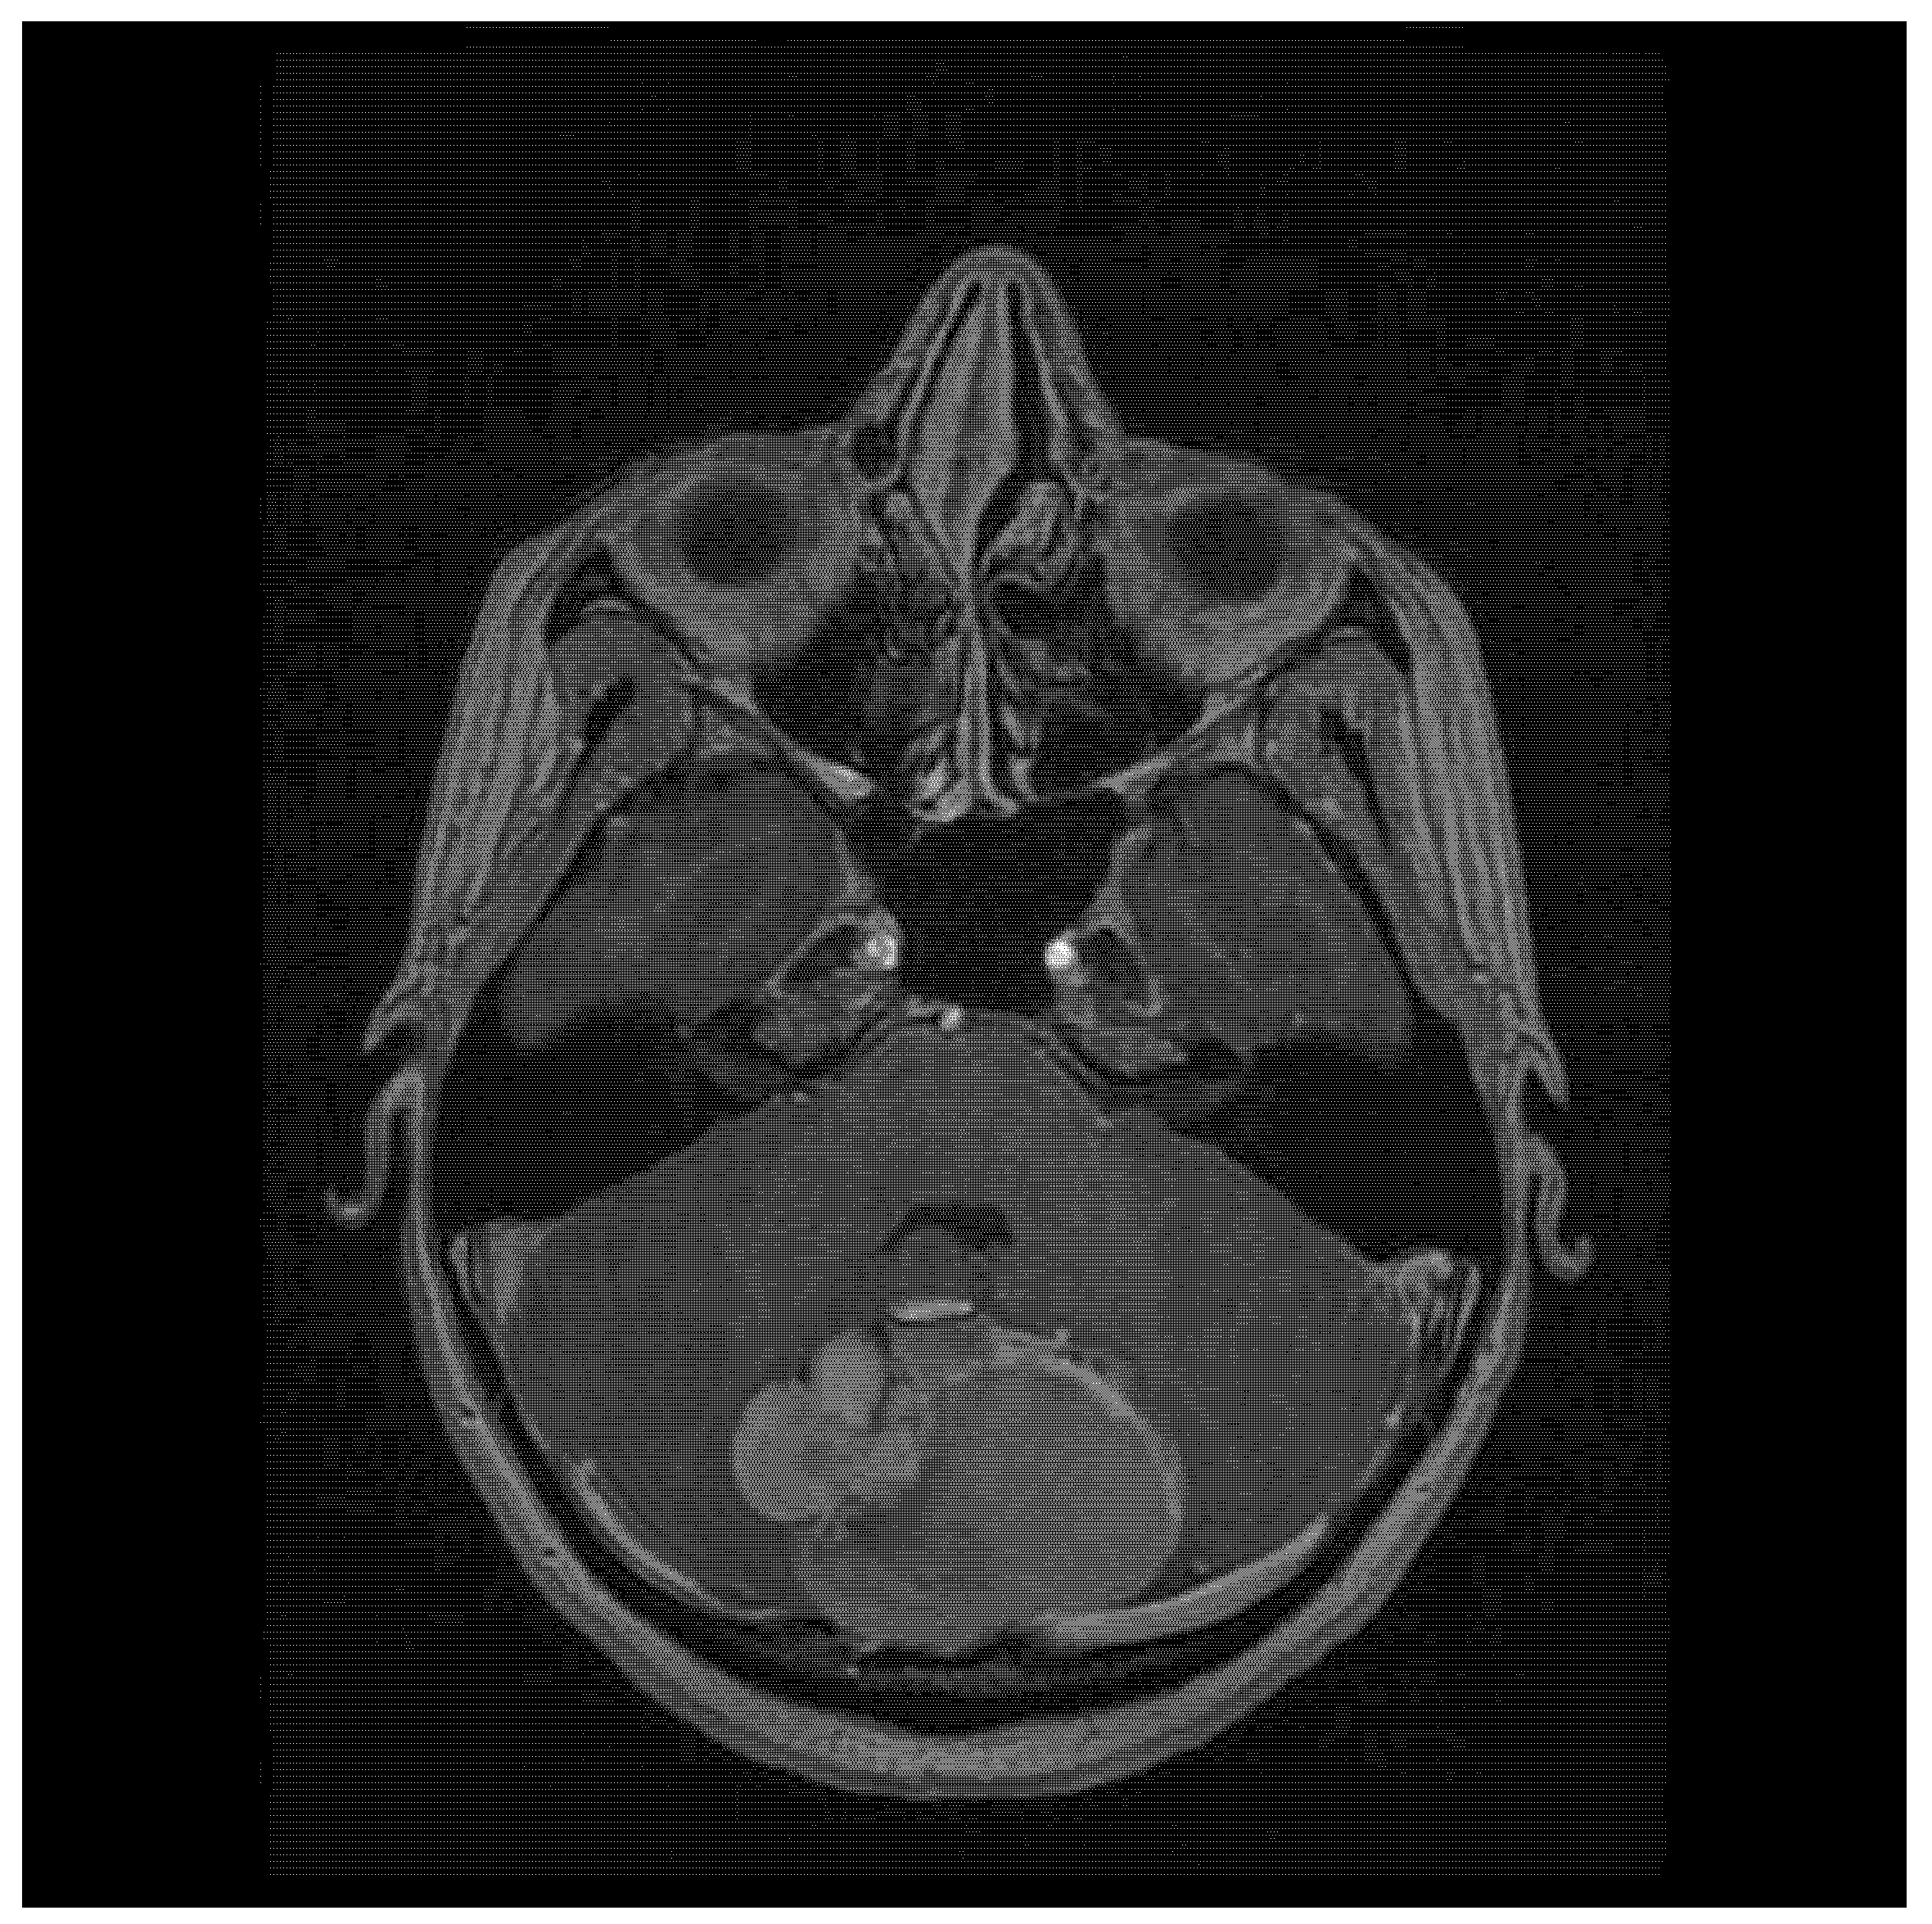

| 22/female | cerebellum—midline | mature teratoma | severe headache | current case |